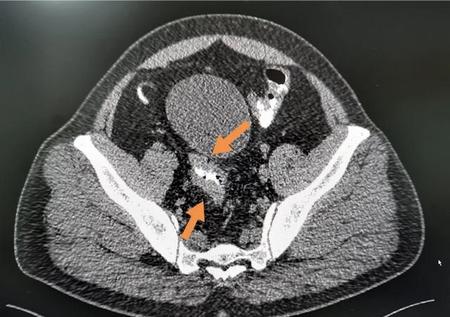

这是一位乙状结肠癌,不完全性肠梗阻,开刀切除肿瘤解除梗阻,十天左右就出院了。